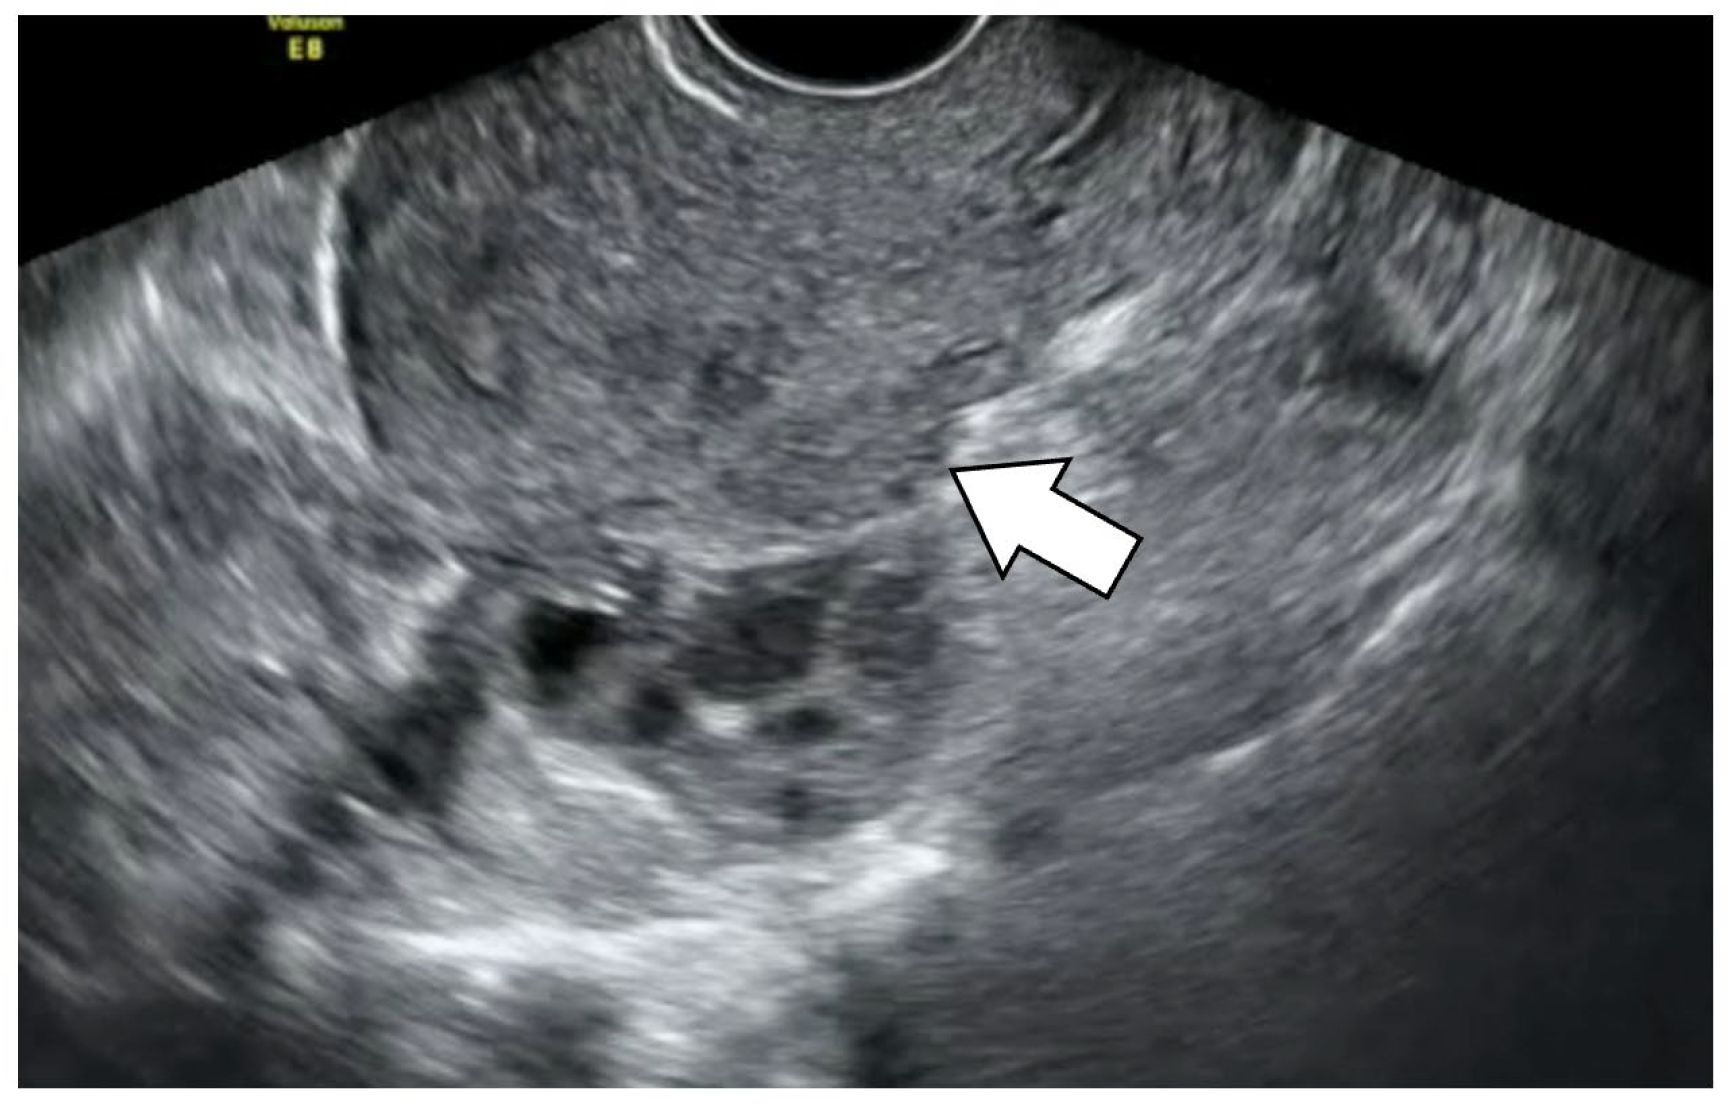

- Hensen, J.H.; Puylaert, J.B. Endometriosis of the posterior cul-de-sac: Clinical presentation and findings at transvaginal ultrasound. Am. J. Roentgenol. 2009, 192, 1618–1624. [Google Scholar] [CrossRef] [PubMed]

- Chiu, L.C.; Leonardi, M.; Lu, C.; Mein, B.; Nadim, B.; Reid, S.; Ludlow, J.; Casikar, I.; Condous, G. Predicting Pouch of Douglas Obliteration Using Ultrasound and Laparoscopic Video Sets: An Interobserver and Diagnostic Accuracy Study. J. Ultrasound Med. 2019, 38, 3155–3161. [Google Scholar] [CrossRef]